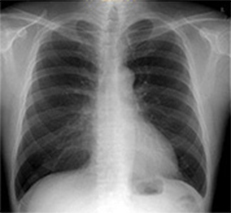

胸部経時差分処理

Temporal Subtraction処理

Temporal Subtraction処理は、独自のアルゴリズム補正をもとに、胸部画像の現在と過去の差分画像を生成する画像処理技術です。

そこで、現在と過去の差分画像を生成し「変化の有無」を可視化することで、診断精度の向上と時間短縮が期待でき、胸部読影を強力にサポートします。

◆変化が可視化され、新規病変の認識がしやすくなる。

◆肺門部や心臓裏の見落としやすい部位の病変が見つけやすくなる。

◆過去画像と現在画像の比較により経時的変化が画像化され、経過観察が容易になる。